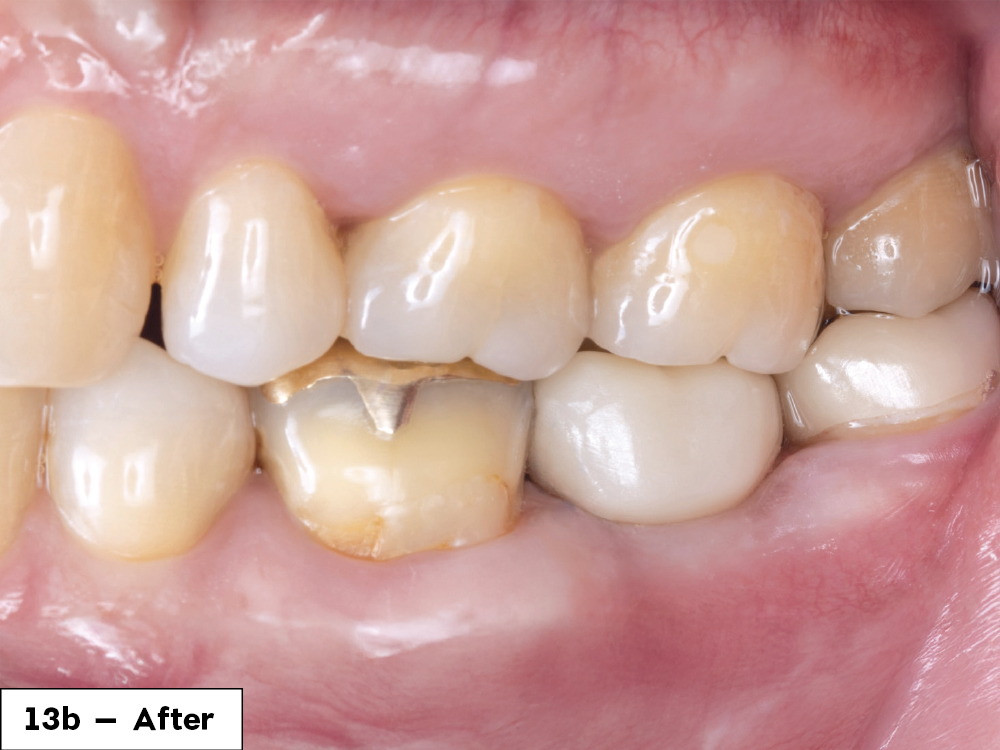

In-office milling is a quickly evolving option for the modern dental practice. With the introduction of a same-day screw-retained option, BruxZir® NOW SRC milling blocks, there’s even more opportunity for optimizing single-unit restoration workflows. In this case study, I’ll demonstrate how this product can be used as part of an efficient workflow for tooth replacement in the posterior. When combined with guided surgery and in-office crown design, this procedure offers reliable results while saving money and significantly cutting down on chair time for dentists.